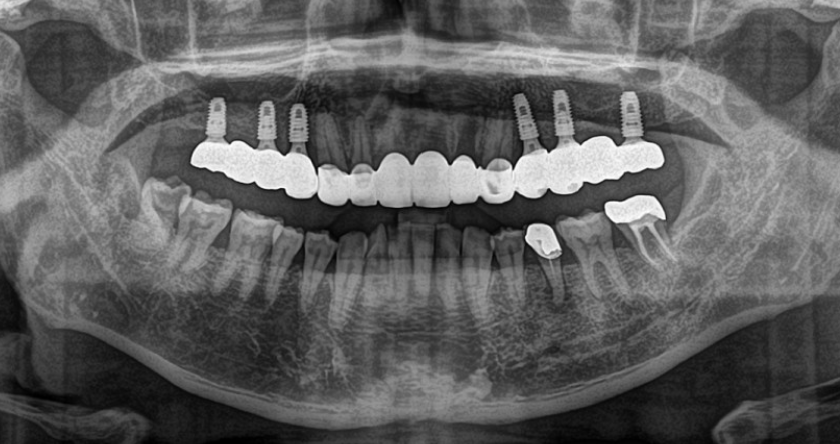

임플란트 시술에 대해 고민이신가요? 정부에서 임플란트 일부 비용을 지원해 주는 복지 혜택을 제공하고 있습니다. 이번 기회에 정부 보조금을 지원받아 아프셨던 치아 통증 참지마시고 임플란트 시술을 하시길 바랍니다. 아래 링크를 통해 임플란트 정부 지원금 혜택 받으시길 바랍니다.